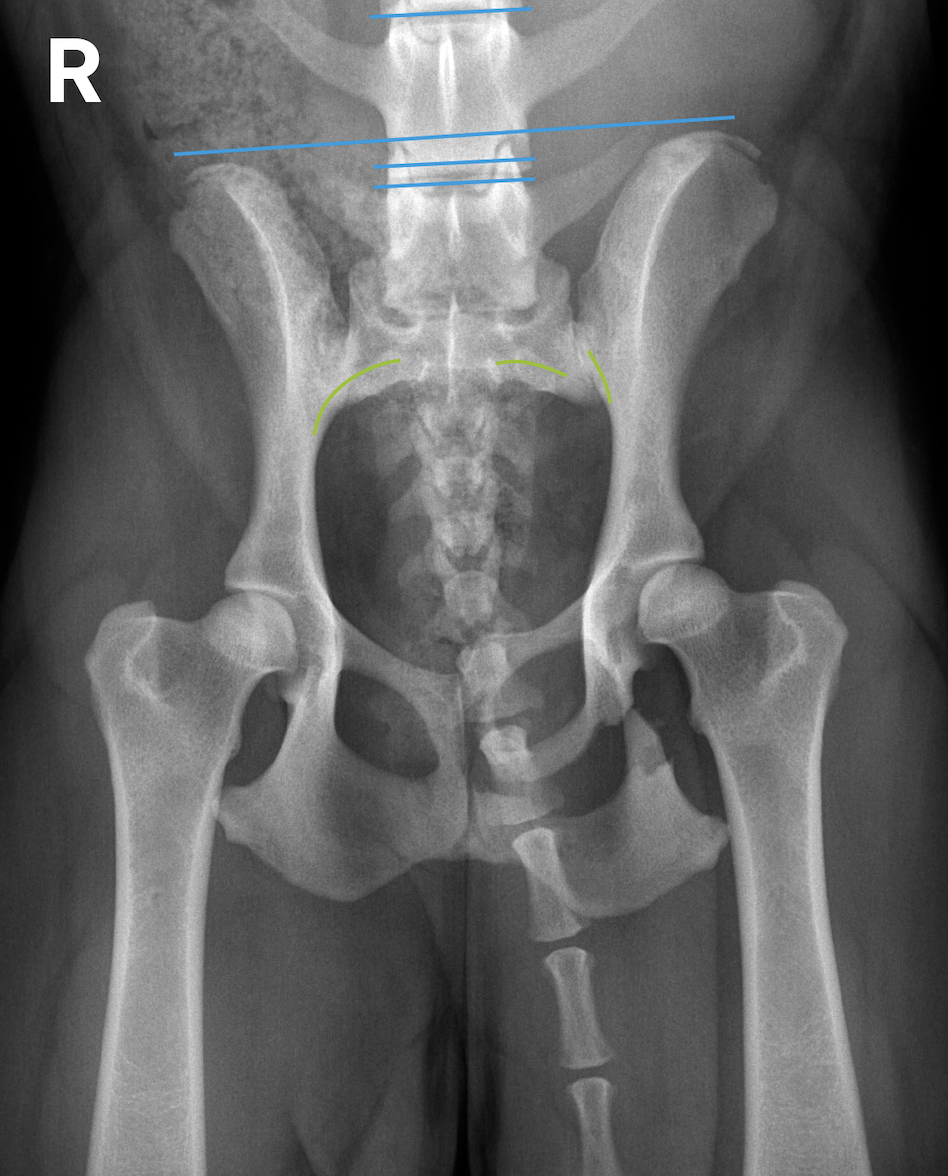

In Folge eines Autounfalls erlitt ein 2 Jahre alter Podenco (weiblich) ein Trauma und kann seitdem nicht mehr gehen. Auch stehfähig ist der Patient nur mit Unterstützung. Der klinische Befund ist links schlechter als rechts. Der Röntgenbefund zeigt eine Schambein- und Sitzbeinfraktur links mit Symphysenfraktur bzw. Symphysiolyse. Zu erkennen ist eine bilaterale iliosakrale Luxation mit langerungsbedingt variabler Darstellung. Die Aufnahmen geben damit Antwort auf die nach einem Unfall häufige Frage, ob das Iliosakralgelenk luxiert ist und eine Diastase vorliegt oder nicht. Eine normale anatomische Situation zeigt stufenlose Gelenkflächenkonturen von Darmbein (Ilium) und Sakrumflügel sowie einen schmalen Gelenkspalt.

• Ein Vergleich der Parallelität einer Tangente entlang der Darmbeinflügel mit Tangenten entlang der Endplatten der kaudalen Lendenwirbel kann leichte Asymmetrien aufdecken helfen.

• Röntgenaufnahmen sind nur Momentaufnahmen und instabile Luxationen können beim Lagern zur bildgebenden Untersuchung (partiell) reponiert werden, wodurch eine Dislokation oder Instabilität manchmal unterschätzt werden kann.